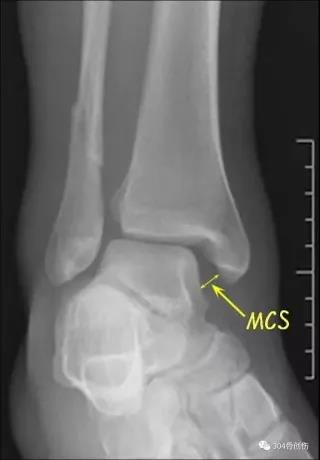

下胫腓联合损伤诊断

术中判断外旋应力试验::内侧间隙增大超过2毫米提示损伤Hook test:在内外踝骨折固定后,用尖钩向外拉腓骨,如腓骨向外移动大于4mm,则表明下胫腓联合韧带完全撕裂